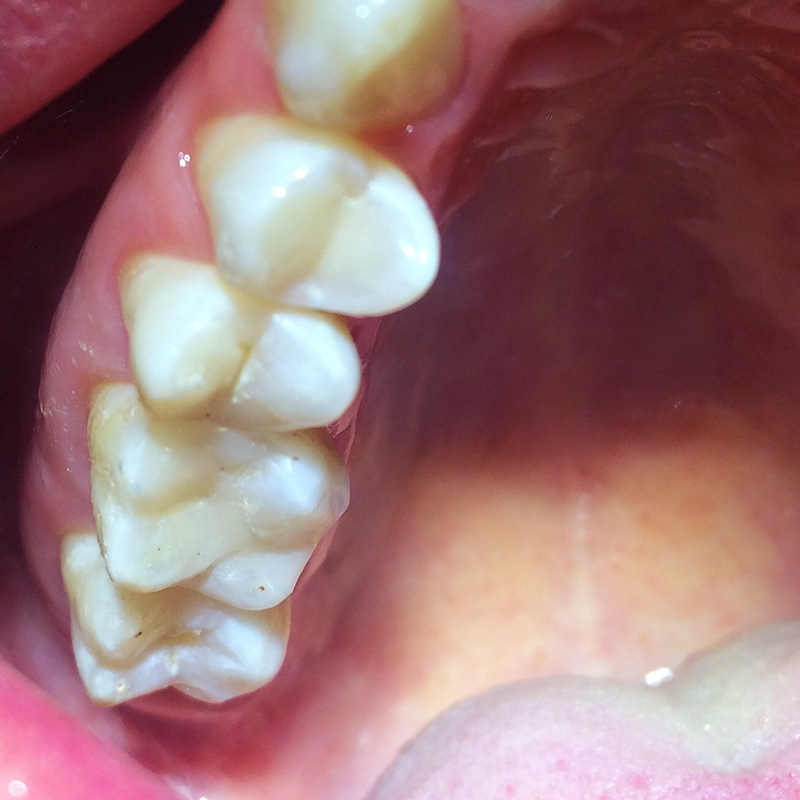

Лечение кариеса зуба 4.6 композитом Filtek Posterior A3Смотреть работуСрок лечения:90 минутСумма лечения:6 000 руб.